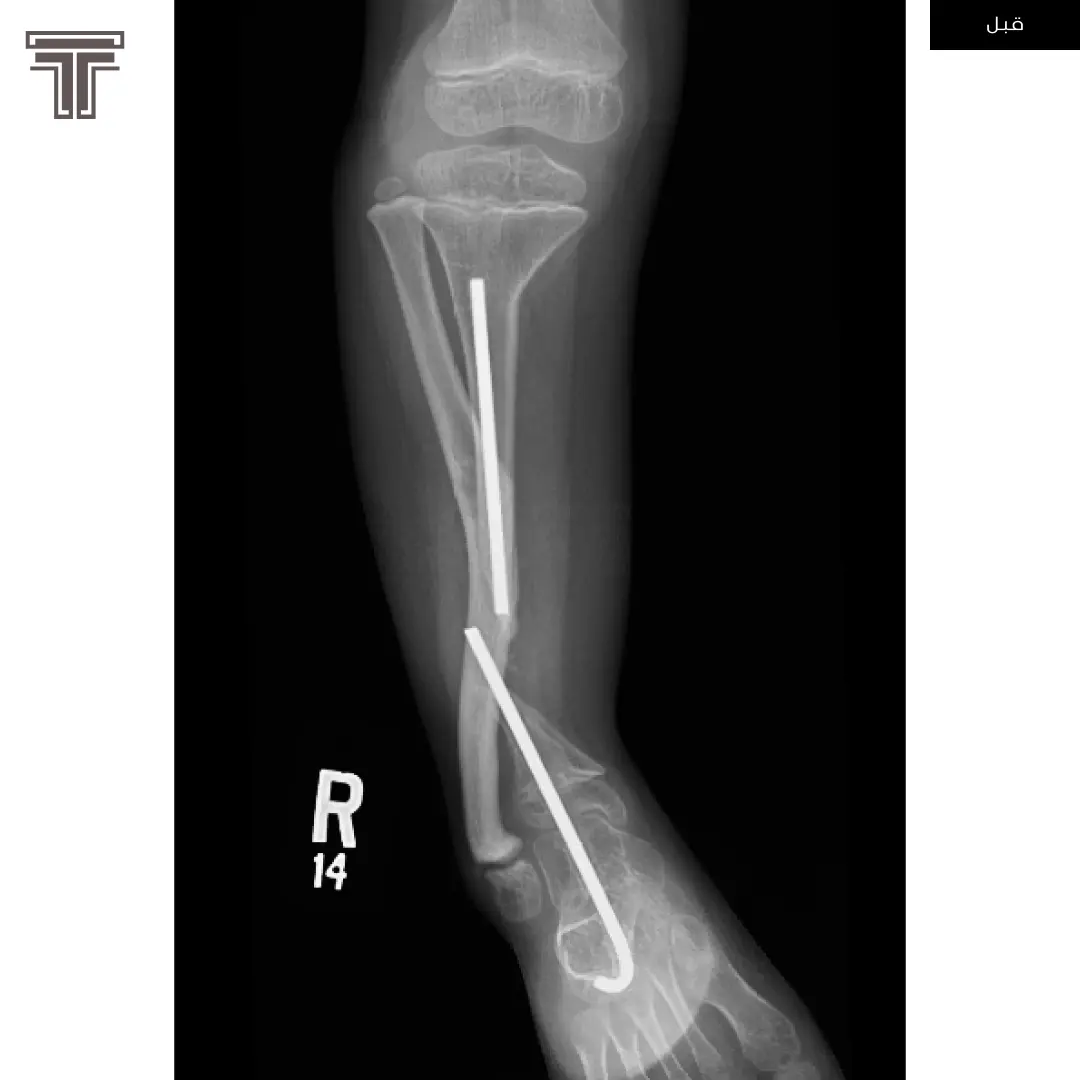

عندما تهمل خلوع الورك الولادية لعمر كبير يصبح علاجها وارجاعها صعب ويتطلب عملية استبدال للمفصل. وفي مثل هذه العمليات وتحديدا في استبدال مفاصل خلوع الورك الولادية يتطلب تقصير في طول الفخذ لتجنب المضاعفات.